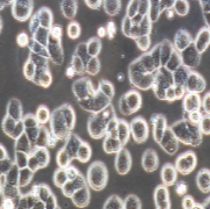

2) 形态:上皮细胞样,贴壁生长

- 细胞形态:

上皮细胞样,贴壁生长